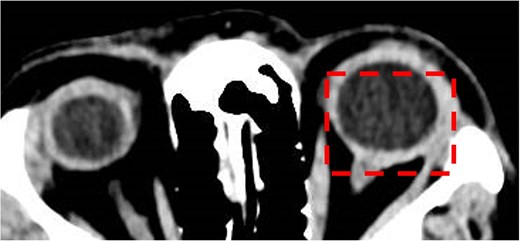

Optical coherence tomography (OCT) confirmed significant left eye macular oedema and elevated retinal nerve fibre layer (RNFL) thickness with an average of 305 μm, in comparison to right eye of 102 μm. B scan revealed left choroidal and scleral thickening, consistent with posterior scleritis, however T sign was not present. Systemic investigations did not suggest other secondary autoimmune or infectious aetiologies. Routine blood tests (full blood count, kidney and liver function, inflammatory markers) were normal, as well as erythrocyte sedimentation rate, angiotensin converting enzyme, IgA, IgG, QuantiFERON gold assay for Mycobacterium tuberculosis, syphilis serology, antinuclear antibody, antineutrophil cytoplasmic antibody, and human leukocyte antigen (HLA)-B27. Chest radiograph showed no evidence of hilar lymphadenopathy. Computed tomography brain and orbits with contrast confirmed the diagnosis of scleritis, with diffuse thickening of the left sclera with contrast enhancement when compared to the right, as demonstrated in Fig. 1.

Computed tomography brain and orbits with contrast. Axial image demonstrating posterior scleritis in the left eye (dashed box).